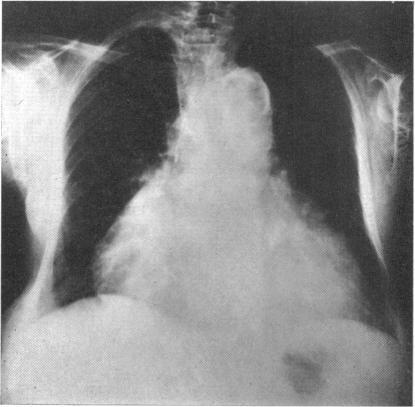

BEDFORD D E

Br Heart J. 1964 Jul;26(4):499-512. doi: 10.1136/hrt.26.4.499.